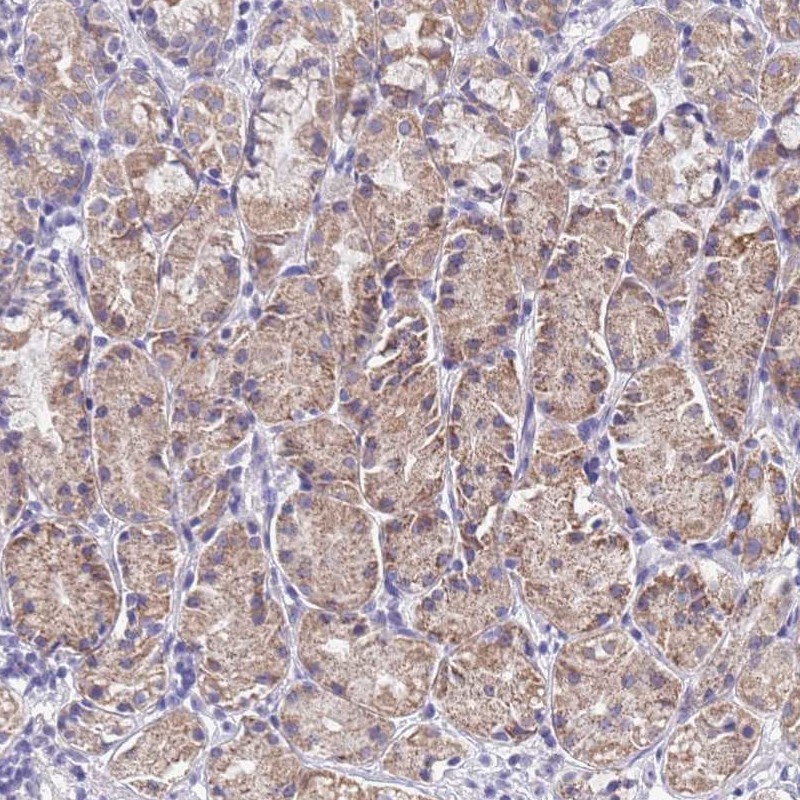

Immunohistochemical staining of human stomach shows cytoplasmic positivity in glandular cells.